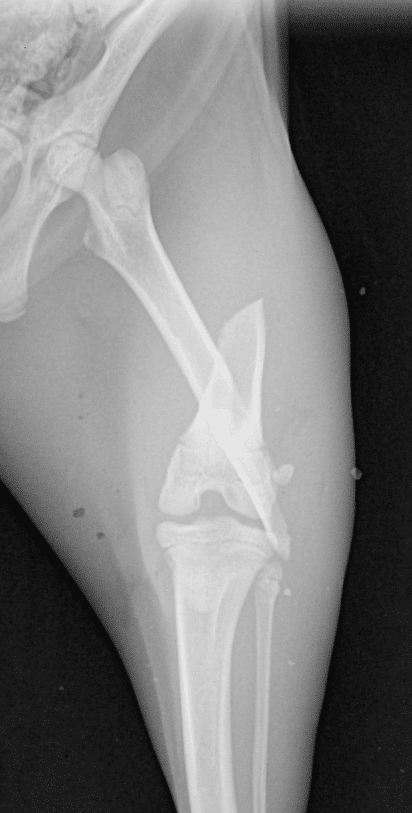

Les fractures chez le chat